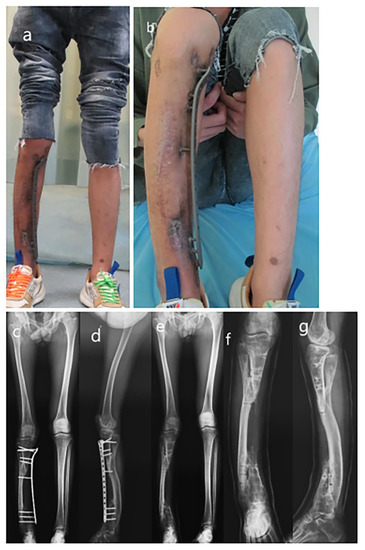

Figure 3.

Removal of Ilizarov apparatus and externalized LCP. (a) AP view radiograph before removal of Ilizarov apparatus; (b) Lateral view radiograph before removal of Ilizarov apparatus; (c) AP view radiograph of externalized LCP fixation; (d) Lateral view radiograph of externalized LCP fixation.